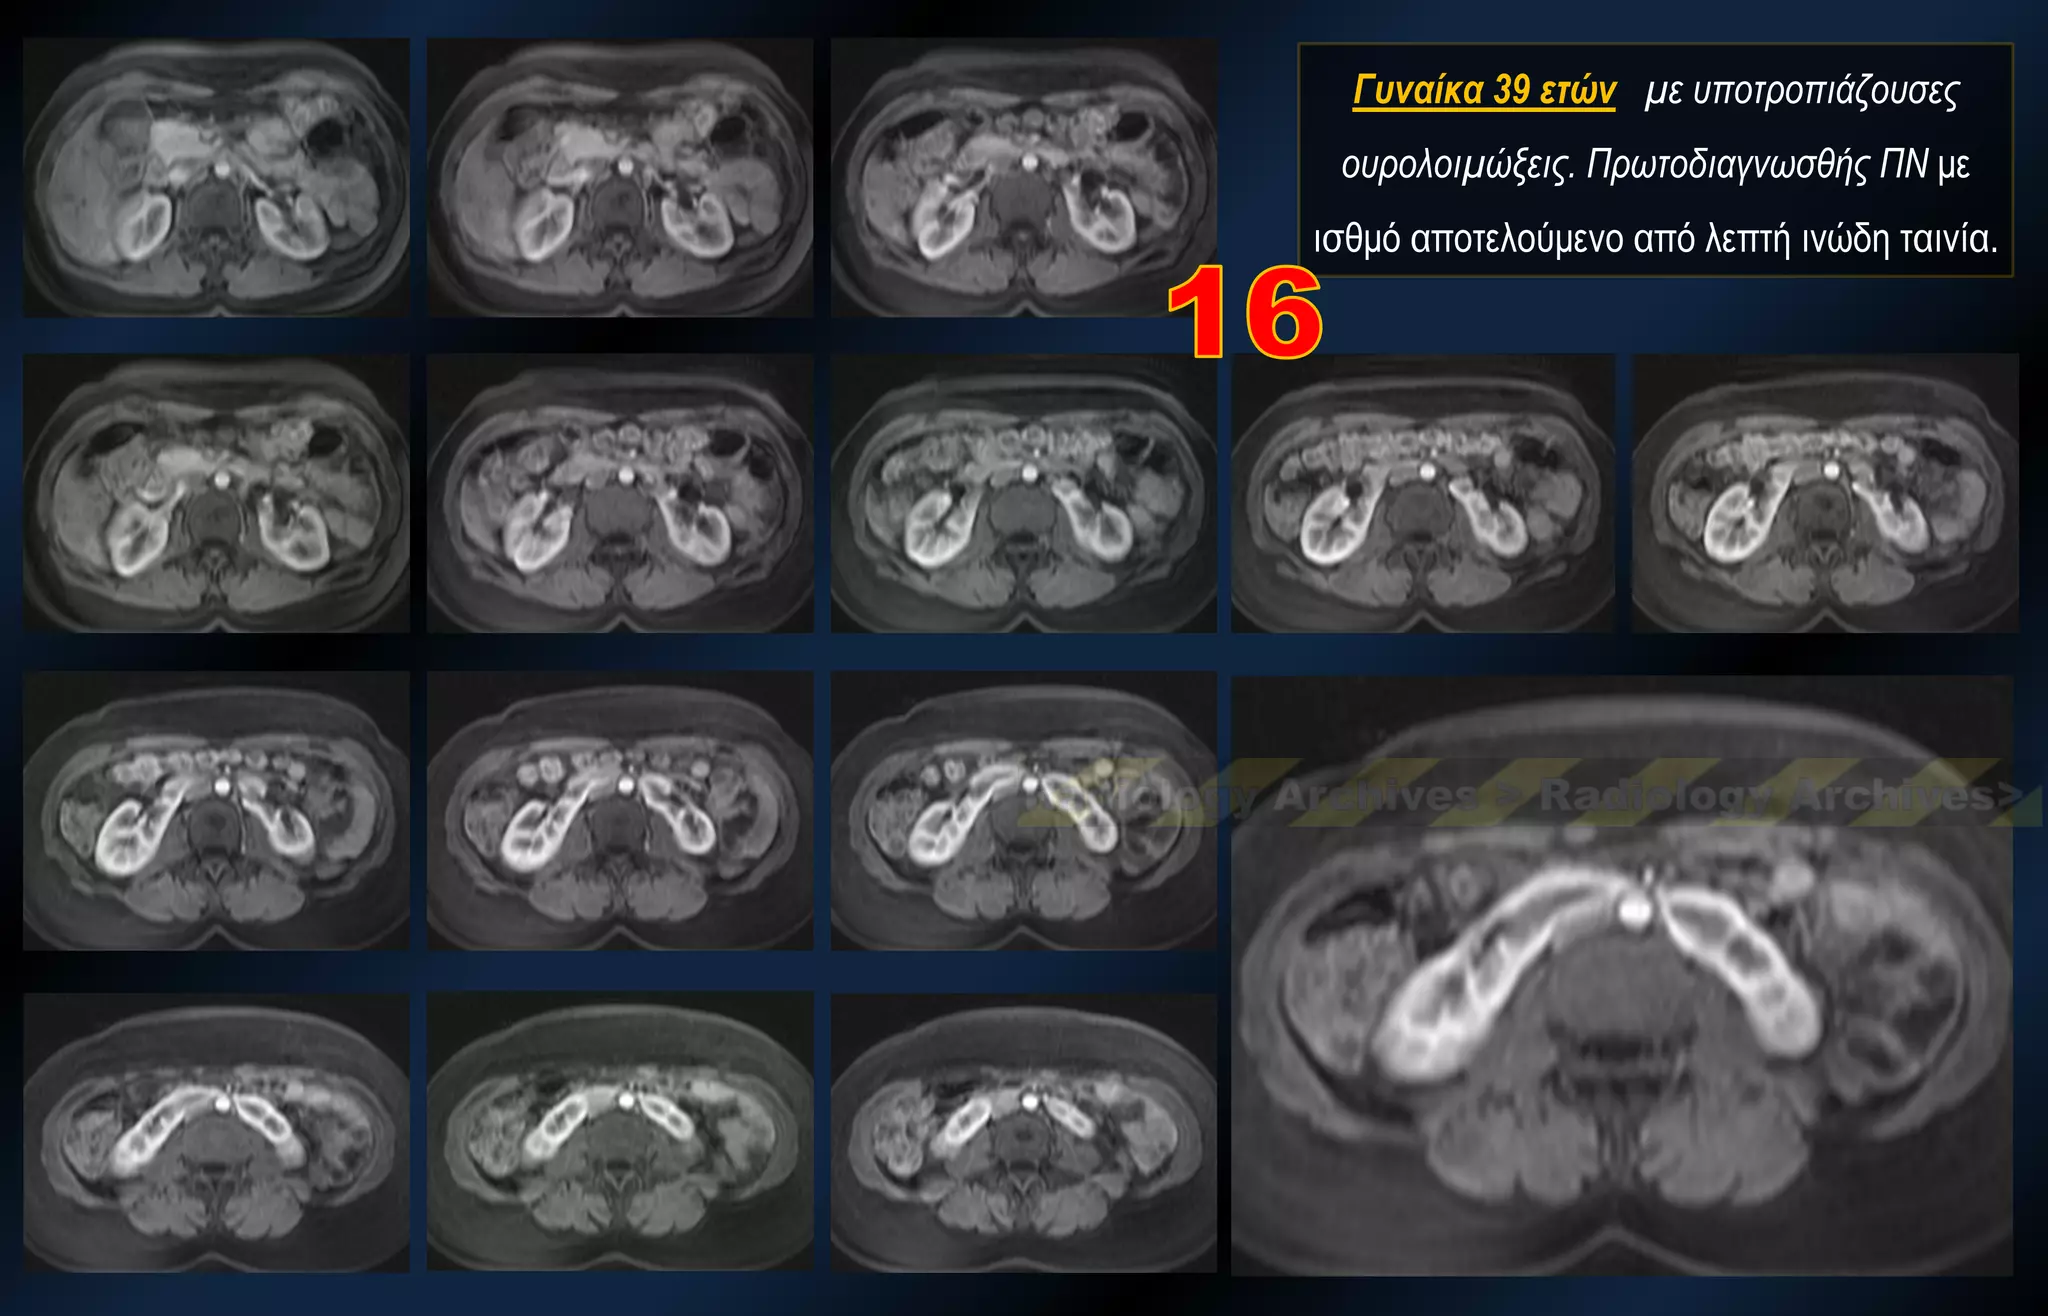

Γυναίκα 39 ετών με υποτροπιάζουσες ουρολοιμώξεις. Πρωτοδιαγνωσθής ΠΝ με ισθμό αποτελούμενο από λεπτή ινώδη ταινία.

Γυναίκα 39 ετώνμε υποτροπιάζουσες ουρολοιμώξεις. Πρωτοδιαγνωσθής ΠΝ με ισθμό αποτελούμενο από λεπτή ινώδη ταινία.